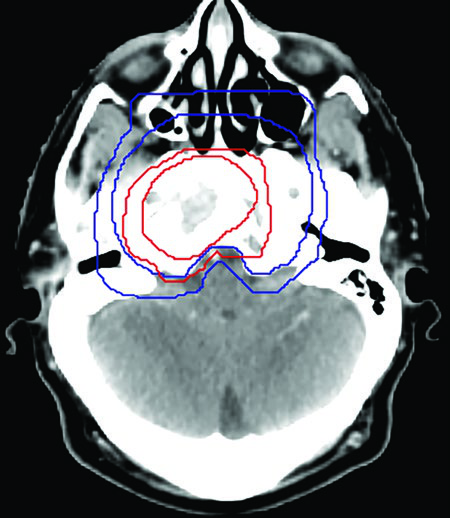

Caso 2: T4N2 EBV positivo

Paciente con enfermedad localmente avanzada, extensión intracraneal a través del foramen oval y seno cavernoso ipsilateral, adenopatías bilaterales en niveles II-V. El GTV70 incluyó el tumor primario con toda su extensión intracraneal visible en RM T1 con gadolinio, así como el conglomerado ganglionar necrótico. El CTV70 se expandió 5 mm en la mayoría de las direcciones, reduciéndose a 0 mm en la interfaz con el lóbulo temporal. El CTV subclínico requirió la inclusión del seno esfenoidal completo, el clivus completo, la cavidad de Meckel bilateral y todos los niveles cervicales bilaterales hasta la grasa posterior a la clavícula en el nivel V.

Ambos casos fueron tratados con quimiorradioterapia concurrente con cisplatino, esquema SIB en 33 fracciones (70 Gy al PTV70, 56 Gy al PTV56), con verificación mediante CBCT diario.